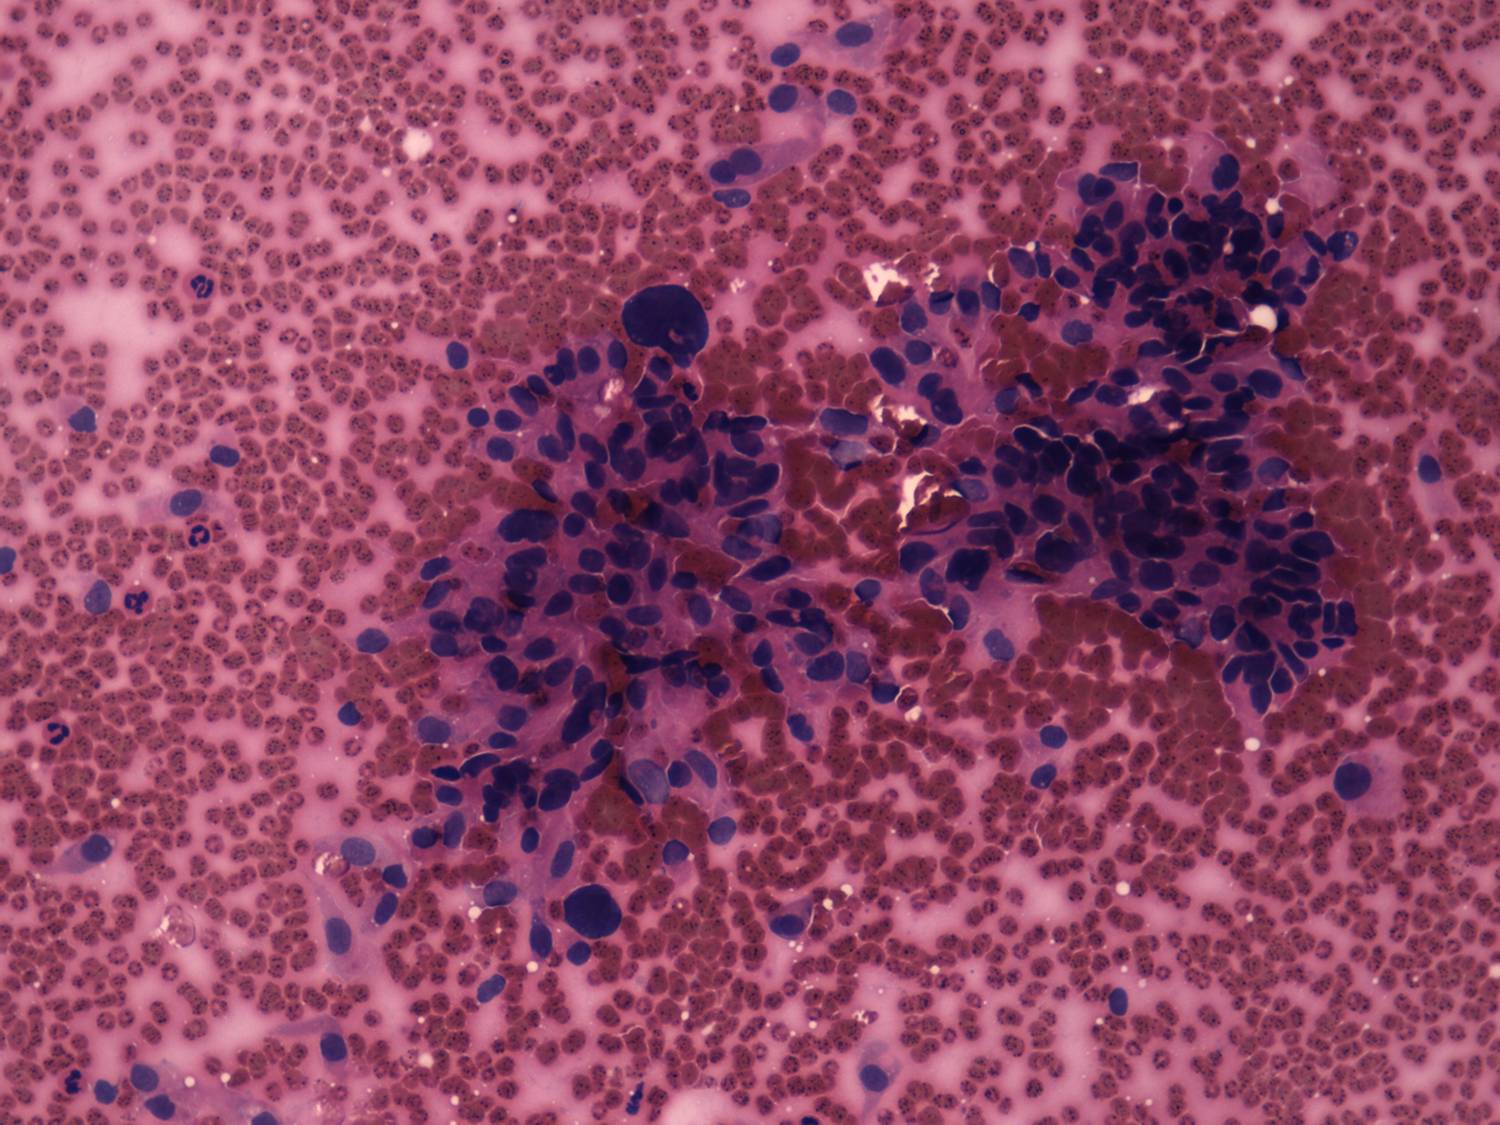

The borders of the nodule - case 638 (cytologic picture 2)

H.-E. smear, 200x.   Atypical pleomorphic forms are demonstrated.